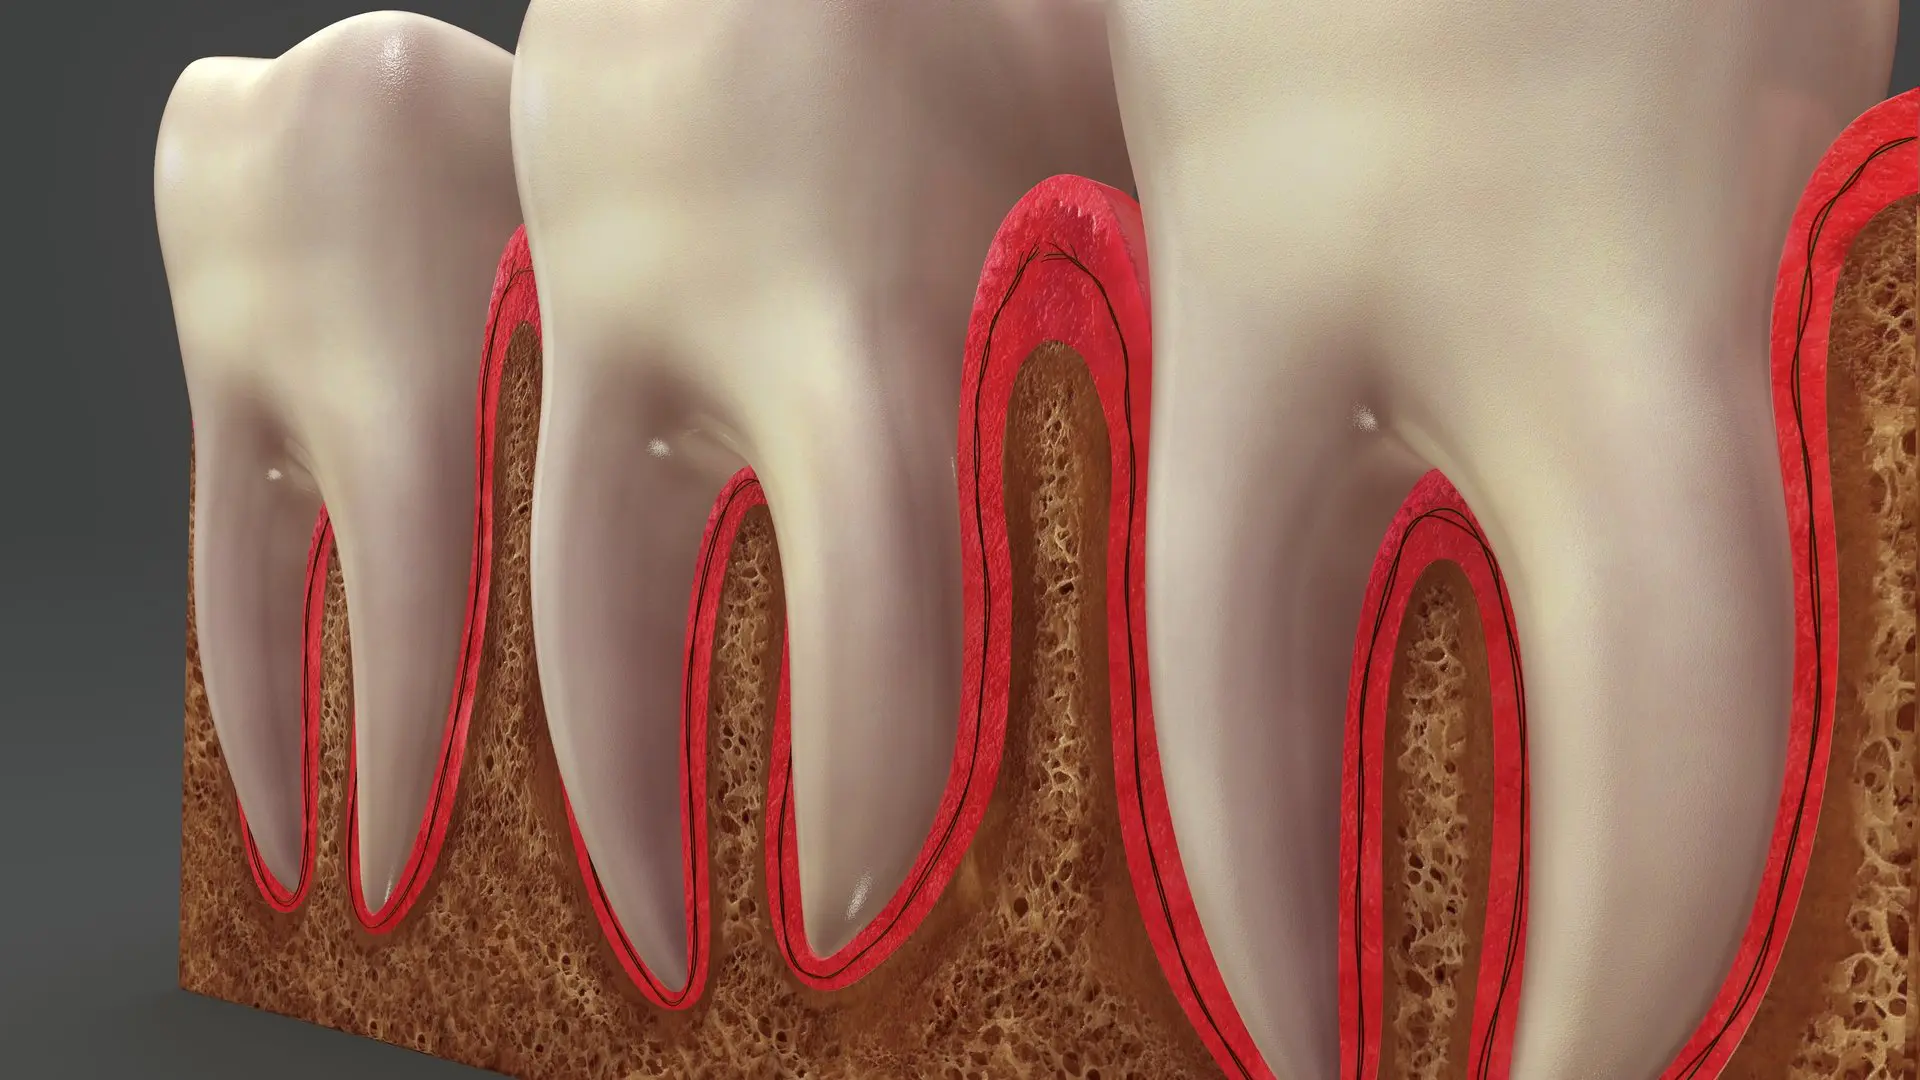

The term “root canal” has a couple different meanings. It refers to the actual passages within the tooth between the pulp and the tooth roots that contain nerves and blood vessels. Once an adult tooth has emerged from the gums, the tooth’s nerve doesn’t serve a specific purpose other than sensing heat, cold, and other stimuli. When the pulp of a tooth becomes infected, it is standard procedure to eliminate the infection and related pain by removing the nerve and the infected pulp inside the tooth. This thorough cleaning the inside of the tooth and subsequent sealing is referred to as a root canal. A root canal cleans out the infected tooth pulp and also disinfects the canals of the tooth.

Once the infection is resolved, the canal is filled in to prevent any further infection. Your tooth has been saved, but because it is no longer a living tooth since the the pulp, nerves and blood vessels have been removed. A dead tooth can be prone to fracture and can become more brittle. To protect your tooth from these new complications, Dr. Varley will restore the tooth with a tooth-colored crown to guard it from injury or infection. A crown is stronger than natural tooth enamel and preserves the structural integrity of the tooth preventing breakage.